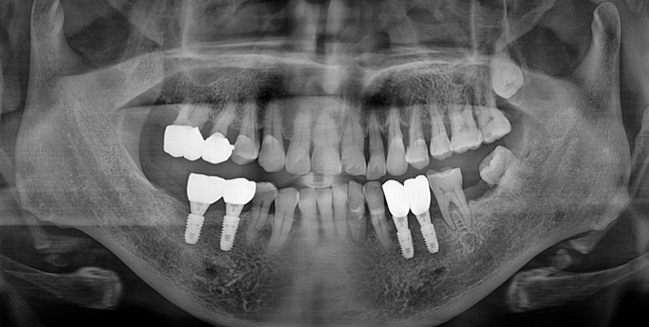

소실된 구치부 지지의 확립.

Before

After

위 케이스 에서는 아래 어금니가 없이 오래 계셔서 위 어금니가 내려오는 정출 현상을 확인 하실 수 있습니다.

너무 늦지 않았다면 이런 어금니들도 크라운으로 씌워서 교합을 맞추고 구치부 지지를 회복할 수 있습니다.